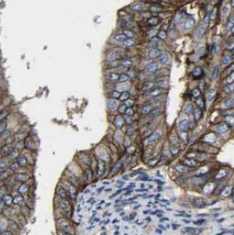

| 验证图片 | Immunohistochemistry of paraffin-embedded human ovary tumor tissue slide using FNab08790(TMEM77 Antibody) at dilution of 1:50 K-562 cells were subjected to SDS PAGE followed by western blot with FNab08790(TMEM77 Antibody) at dilution of 1:600 |